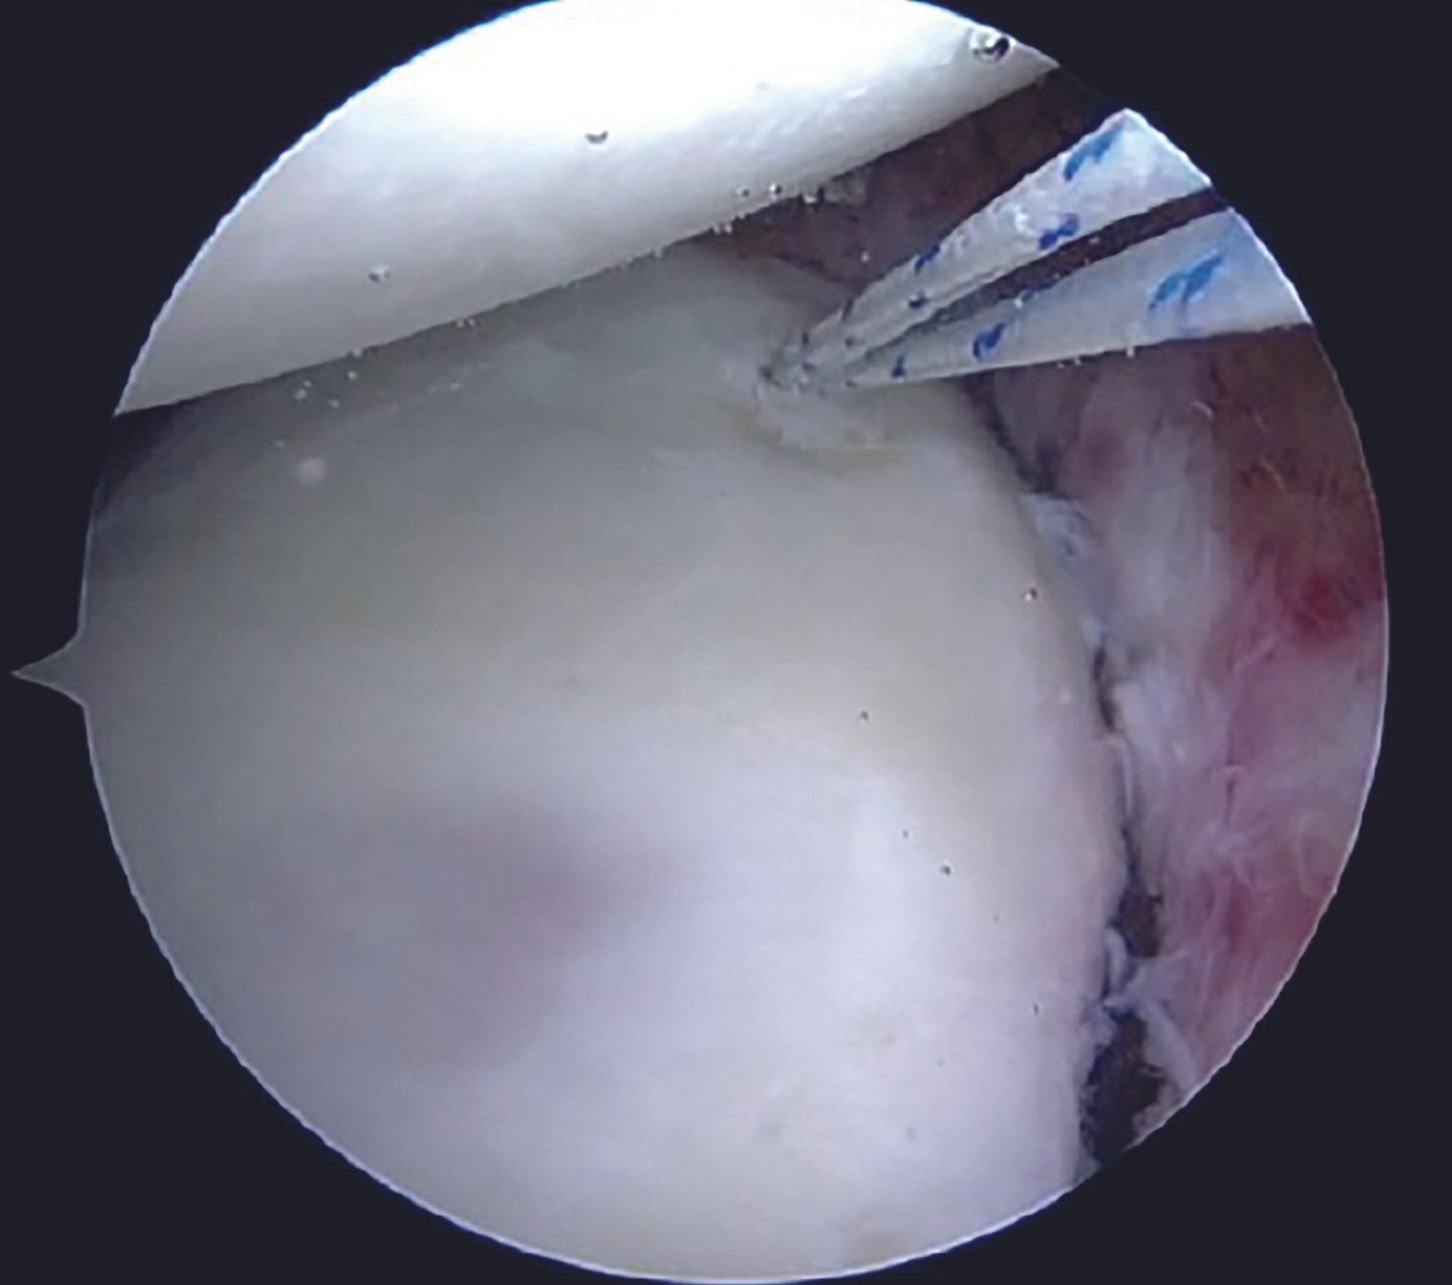

After the diagnostic arthroscopy, viewing portal is switched to the anterosuperior one, whereas the anteroinferior and the posterior portals act as the working portals with 7mm and 5mm cannulae, respectively. Labral tear extent is assessed with a probe (Figure 5).

Capsulolabral tissue is mobilized using 15 and 30 degree arthroscopic tissue elevators sequentially (Figure 6).

Adequate mobilization of the labral tissue from glenoid neck remains a crucial step for an effective Bankart repair. Adequacy of the labral mobilization is indicated by floating of the labral tissue at the level of articular surface of the glenoid. Care should be taken while liberating the labral tissue at 6 O'clock position in order to prevent an injury to the axillary nerve. Frayed tissue at the edge of the glenoid is cleared using a motorized 3.5mm arthroscopic shaver (Figure 7). Anterior glenoid bony surface is freshened with the help of a rasp in order to promote healing (Figure 8).